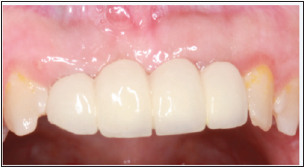

A 19-year-old Saudi male patient diagnosed with a Seckel syndrome reported to the clinic for replacement of upper anterior teeth #12, #11, #21, #22 (Figure 1). He was born to healthy, consanguineous (first cousins) parents. Patient’s mother reported that he was suffering psychologically because of his appearance and his inability to speak properly. Radiographic examination revealed that the remaining permanent teeth have erupted with minimal root development (Figure 2). Periodontal examination showed generalized moderate marginal gingivitis (Plaque score 35%, Bleeding score 15%). Oral hygiene regimen was given to the mother and full mouth gross scaling was performed. Informed consent was obtained for restoring missing teeth with dental implants. Medical clearance was achieved and implants were placed under nitrous oxide sedation and local anesthesia. A variety of tracheal tubes were at hand as many of these young patients have smaller trachea than would be suspected by age and physical size. A full mucoperiosteal flap was raised (Figure 3) and two implants (3.3x8BL- SLActive (Straumann –ITI) were placed in the area of #12 and 22 (Figure 4). Implant sites were grafted buccaly with bone graft (Puros Allograft –Cortico cancellous, Tutogen, Zimmer Dental) and covered with resorbable membrane (Copios pericardium – RTI Biologics, Tutogen, Zimmer Dental). Flap was repositioned and sutured with 4-0 resorbable Vicryl suture (Figure 5). Peri-apical radiograph was taken to show the position of the 2 implants in the edentulous sites (Figure 6). Three months post implantation period, the site was examined for bone and soft tissue healing around the implants to ensure osseointegration. A four-unit implant supported screwretained porcelain fused to metal bridge was attached (Figure 7) and peri-apical radiograph was taken to ensure complete and accurate fitting of the bridge (Figure 8). Occlusion was checked and oral hygiene instructions were given to the mother. The case was followed up for three years (Figure 9). The osseointegration was excellent with no untoward findings. Also, upon follow up, it was noted that the patient was considerably happier and the mother reported that the procedure has changed her son’s life. To the best of the author knowledge, this is the first report of implant supported fixed partial denture in Seckel Syndrome patient [4,7-10].

Figure 7: Insertion of a screw retained 4-units PFM bridge supported by the 2 implants at #12, 22

Figure 8: Insertion of a screw retained 4-units PFM bridge supported by the 2 implants at #12, 22

Figure 9: Insertion of a screw retained 4-units PFM bridge supported by the 2 implants at #12, 22